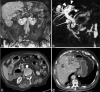

Lemmel's syndrome is a bile duct disease caused by periampullary duodenal diverticula that develop within 2-3 cm of the Vater papilla. This disease manifests itself as nonobstructive jaundice. In most cases, duodenal diverticula do not cause disease, and only in a small percentage of patients, diverticula cause biliary tract obstruction by extrinsic compression. If the compression is severe, in the long term, it can become complicated with lithiasis and cholangitis. Diagnosis is very difficult, and recurrent biliary symptoms must be directly related to the compression of the duodenal diverticula. Imaging is essential for differential diagnosis and includes conventional contrast radiographs, endoscopic retrograde cholangiopancreatography, computed tomography, and magnetic resonance imaging. The investigations show the dilation of the intra- and extra-hepatic bile ducts in the absence of lithiasis or main pancreatic duct dilatation, compressed by the diverticula, which most frequently originate from the medial wall of the second duodenal tract. The treatment of choice is surgical with removal of the diverticula. Failure to diagnose can cause serious health complications for the patient.